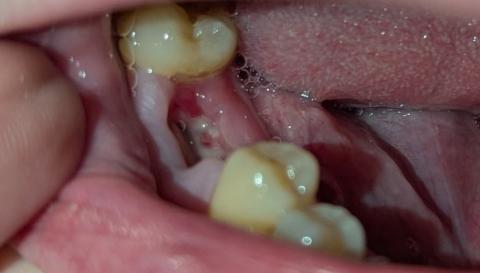

Severe Open Carious Molar With Pulp Exposure Causing Pain, Infection, and Oral Odor

Visual Examination (Zoom 100% – Clinical Findings)

Tooth involved:

Lower posterior molar (likely first or second molar)

Observed conditions:

Extensive crown destruction due to advanced dental caries

Open pulp chamber clearly visible

Dark brown to black necrotic dentin

Two exposed root canal orifices

Food debris and bacterial biofilm present